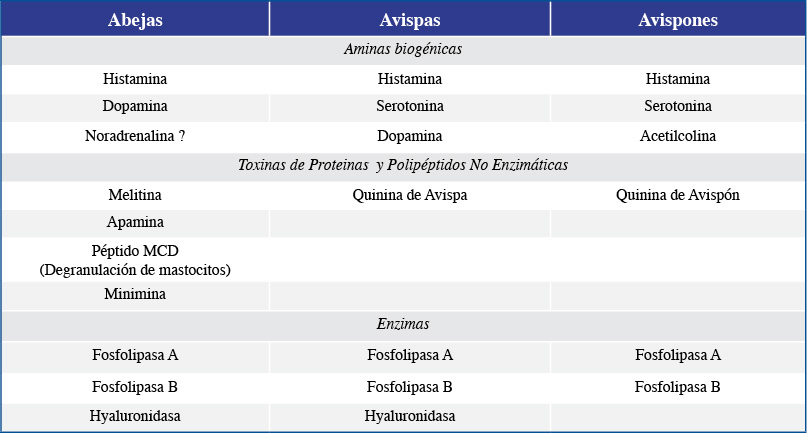

El veneno que inyectan las abejas y las avispas (Tabla No1) siendo semejante, puede diferir en la proporción de sus componentes y en el volumen inyectado, pudiendo esto explicar en algunos casos la toxicidad y magnitud de la respuesta inmuno-alérgica en el individuo afectado; sin embargo el tiempo transcurrido entre la picadura y el inicio terapéutico, la localización de la picadura en el globo ocular y el grado de penetración del aguijón, también son factores determinantes en el pronóstico visual.

Es conocido que los venenos de los himenopteros contienen aminas biológicas (Histamina) causante del dolor, Toxinas poliptídicas no enzimáticas (Melitina-Apamina) y enzimas difusoras (Hialuronidasa y Fosfolipasas)2; es aceptado que de las toxinas no enzimáticas que componen el veneno, es la Melitina la causante principal del daño a los tejidos oculares; actúa como detergente, rompiendo la permeabilidad de la membrana celular, desencadenando una cascada de eventos que sumados a la acción de los otros componentes en el veneno como la acción neurotóxica de la Apamina, induce el edema corneal, la midriasis, la uveitis anterior, la iritis tóxica, la opacidad del cristalino y la descompensación nal de la córnea si no se detiene a tiempo, la acción tóxica sobre los tejidos oculares